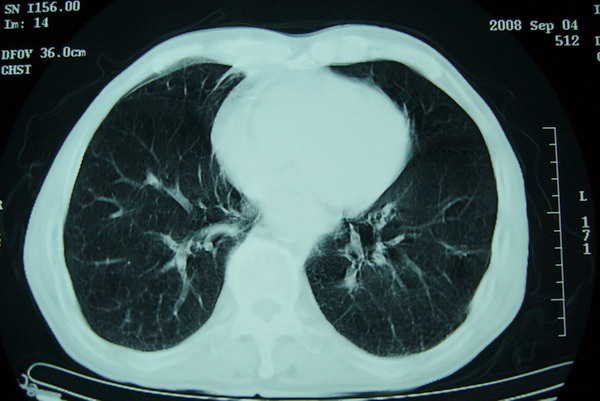

标题: CT15579:男 86岁 咳嗽 咳少量白痰 发热2天 吸烟史60年 [打印本页]

标题: CT15579:男 86岁 咳嗽 咳少量白痰 发热2天 吸烟史60年

右上周围型肺癌,慢支,肺气肿。

分叶及少量边缘性钙化,老年人,周围性肺癌首先考虑。

右上肺一不规则团块,边缘有分叶和毛刺,纵隔有淋巴结肿大。右肺周围性肺癌首先考虑。